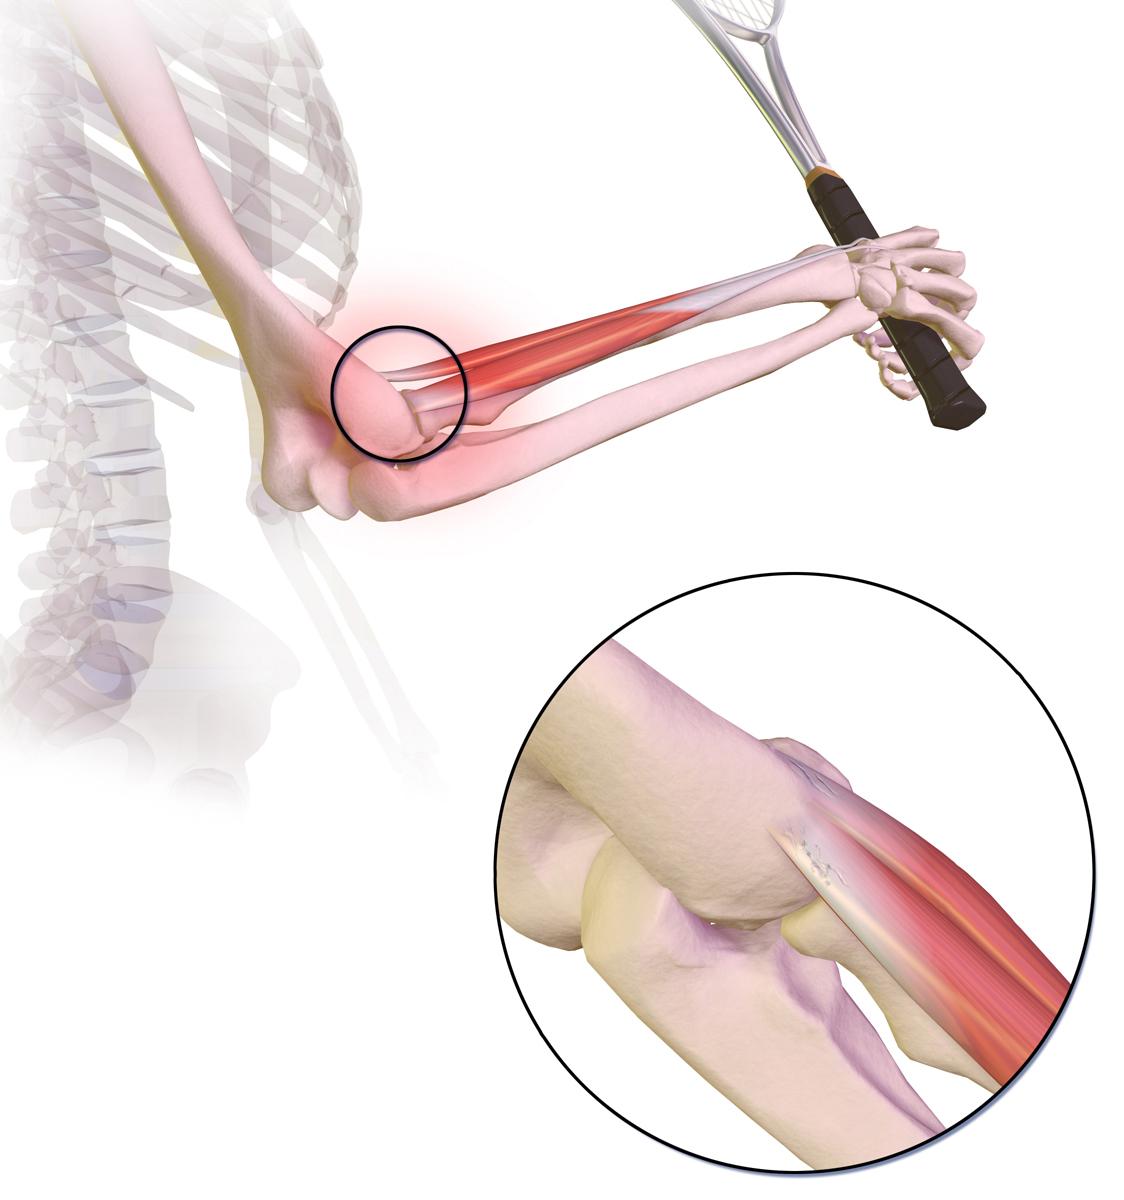

'Tennis elbow' (the medical term is lateral epicondylitis) occurs when the tendons on the outside surface of the elbow get inflamed and sore.

This picture shows where the pain is felt, on the outside of the elbow, in tennis elbow:

Codo de tenista

Por BruceBlaus, CC BY-SA 4.0vía Wikimedia Commons